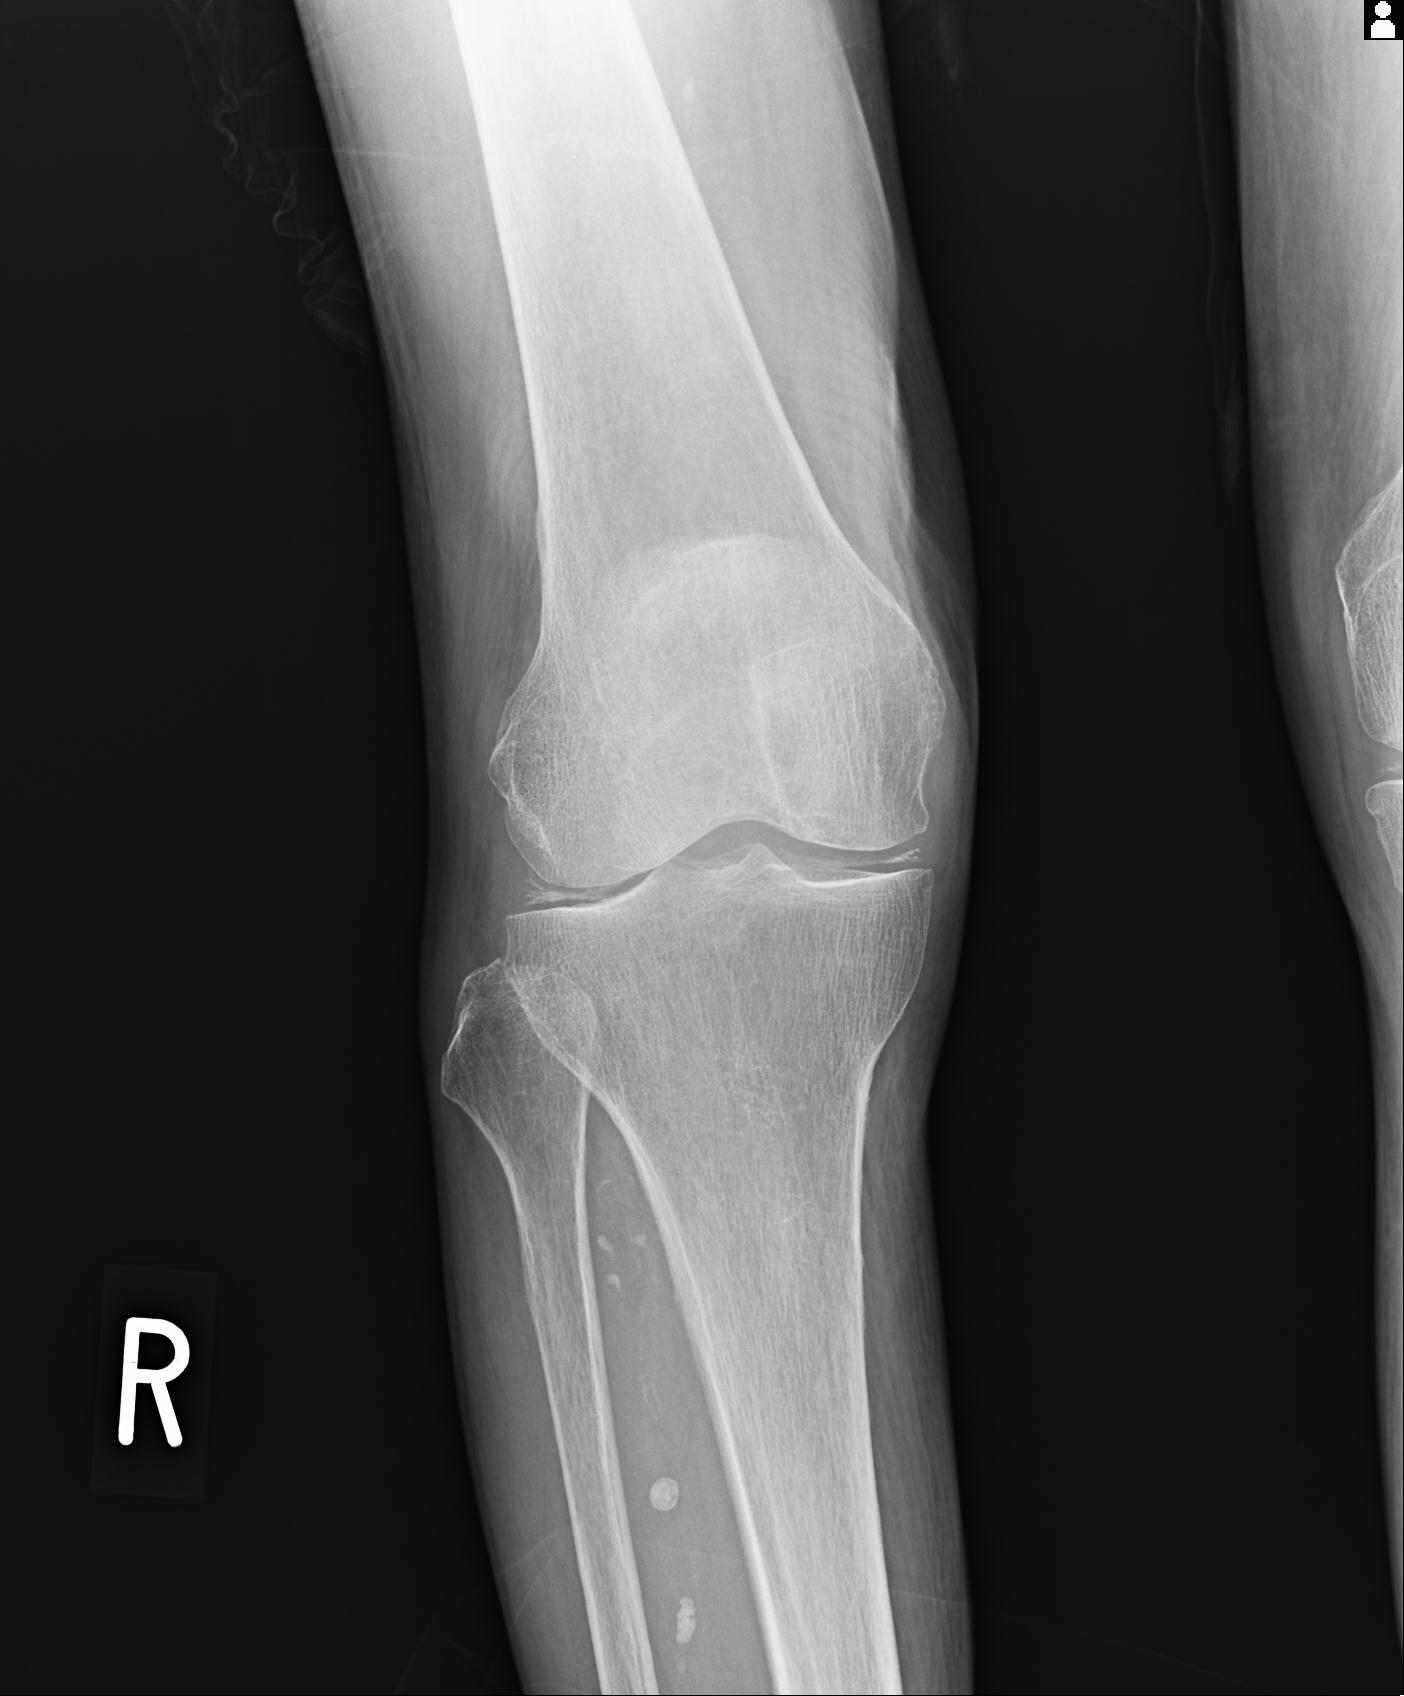

49554 3/13 膝 4R 3/16 4R 1/18 2R 78歳男性 膝蓋骨骨折